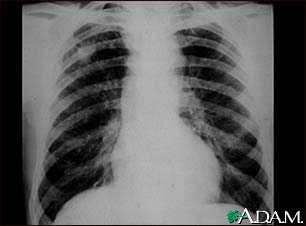

Coal workers pneumoconiosis - stage II #2

This chest X-ray shows coal workers pneumoconiosis - stage II. There are diffuse, small (2 to 4 mm each), light areas throughout both lungs. In the right upper lung (seen on the left side of the picture), there is a light area (measuring approximately 2 cm by 4 cm) with poorly defined borders, representing coalescence (merging together) of previously distinct light areas. Diseases which may explain these X-ray findings include simple coal workers pneumoconiosis (CWP) - stage II, silico-tuberculosis, disseminated tuberculosis, metastatic lung cancer, and other diffuse infiltrative pulmonary diseases.